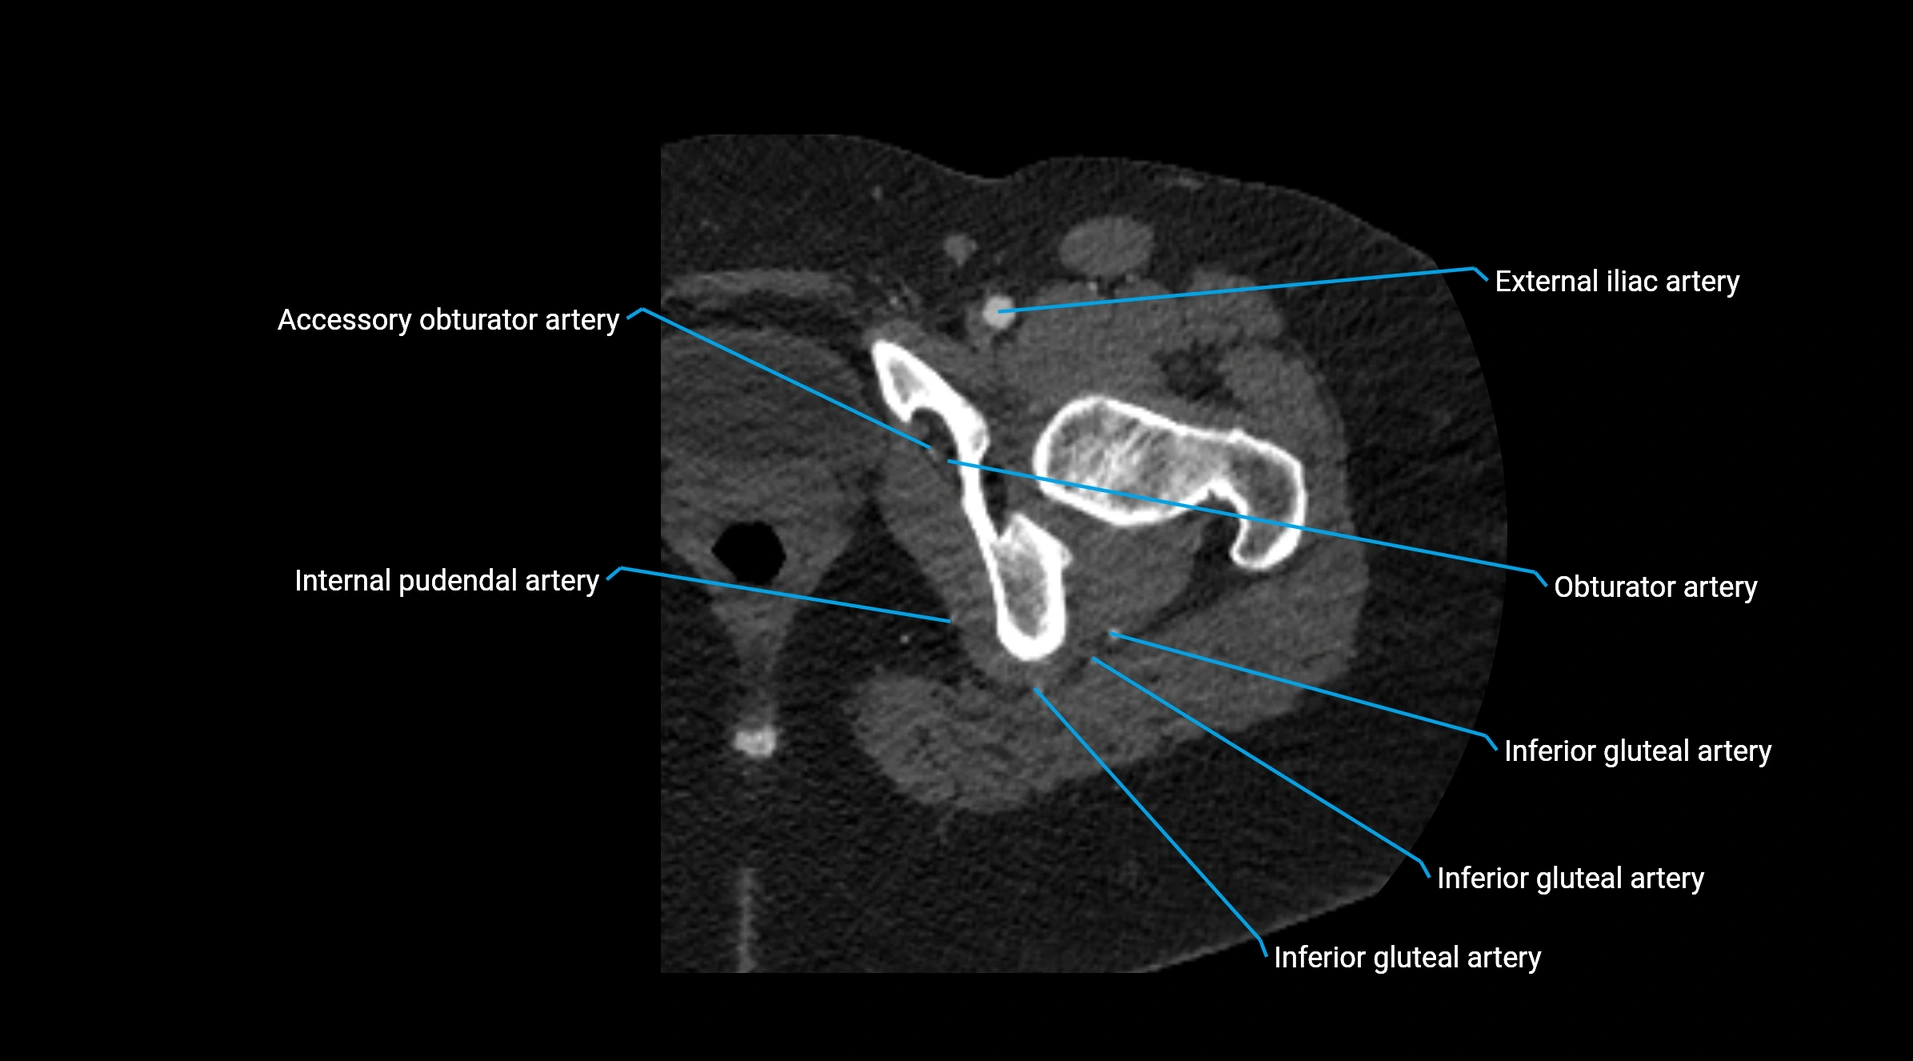

CT Appearance

Non-contrast CT:

• Appears as a tubular soft tissue structure anterior to vertebral bodies

• Calcified atherosclerotic plaques appear as hyperdense foci along the wall

• Useful for screening abdominal aortic aneurysm (AAA) size and mural calcification

Contrast-enhanced CT (CTA):

• Gold standard for abdominal aortic imaging

• Provides excellent detail of lumen, wall, aneurysm, thrombus, and branch vessels

• Multiplanar and 3D reconstructions help in aneurysm measurement, stent graft planning, and dissection evaluation

• Detects acute rupture, traumatic injury, or occlusion with high sensitivity